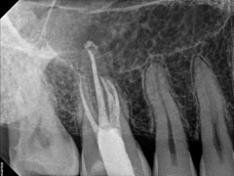

Every tooth has different numbers of roots and canal systems. With the help of magnification and high tech equipment, Dr. Jung can locate and treat the canals including MB2 on upper molars and MM on lower molars.

Apicectomy is the surgical removal of the end portion of a root. To achieve this, access to the root apex is gained via a tissue flap and then bone is removed around the root apex. The aim of apicectomy is to eradicate persistent infection in the periapical tissues and to eliminate the 'apical delta' of root canals that cannot be effectively sealed by conventional endodontics and to excise a root apex that cannot be sealed successfully due to anatomical anomalies such as marked root curvature. Root end will be filled with a medicament called MTA, or Mineral Trioxide Aggregate and finished the procedures.